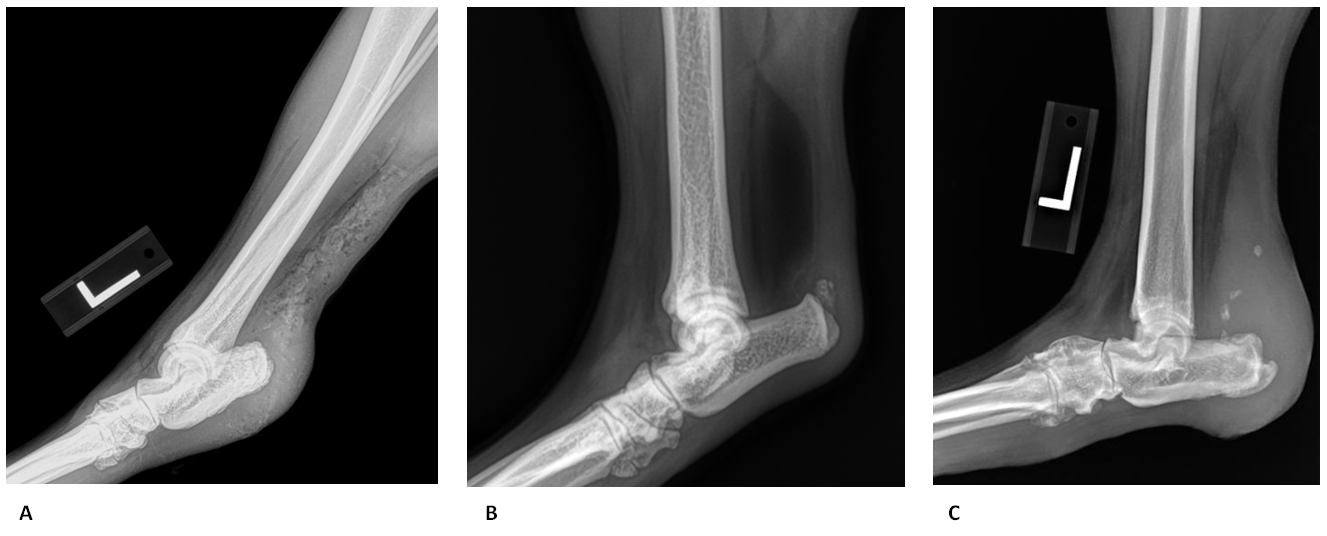

6 7 3 Partial Achilles Tendon Ruptures Ultrasound Cases